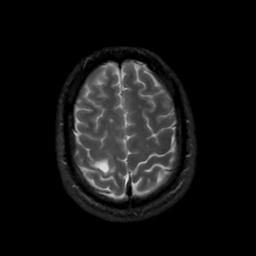

MR Study #8, March 31, 1991 -- Slice #41